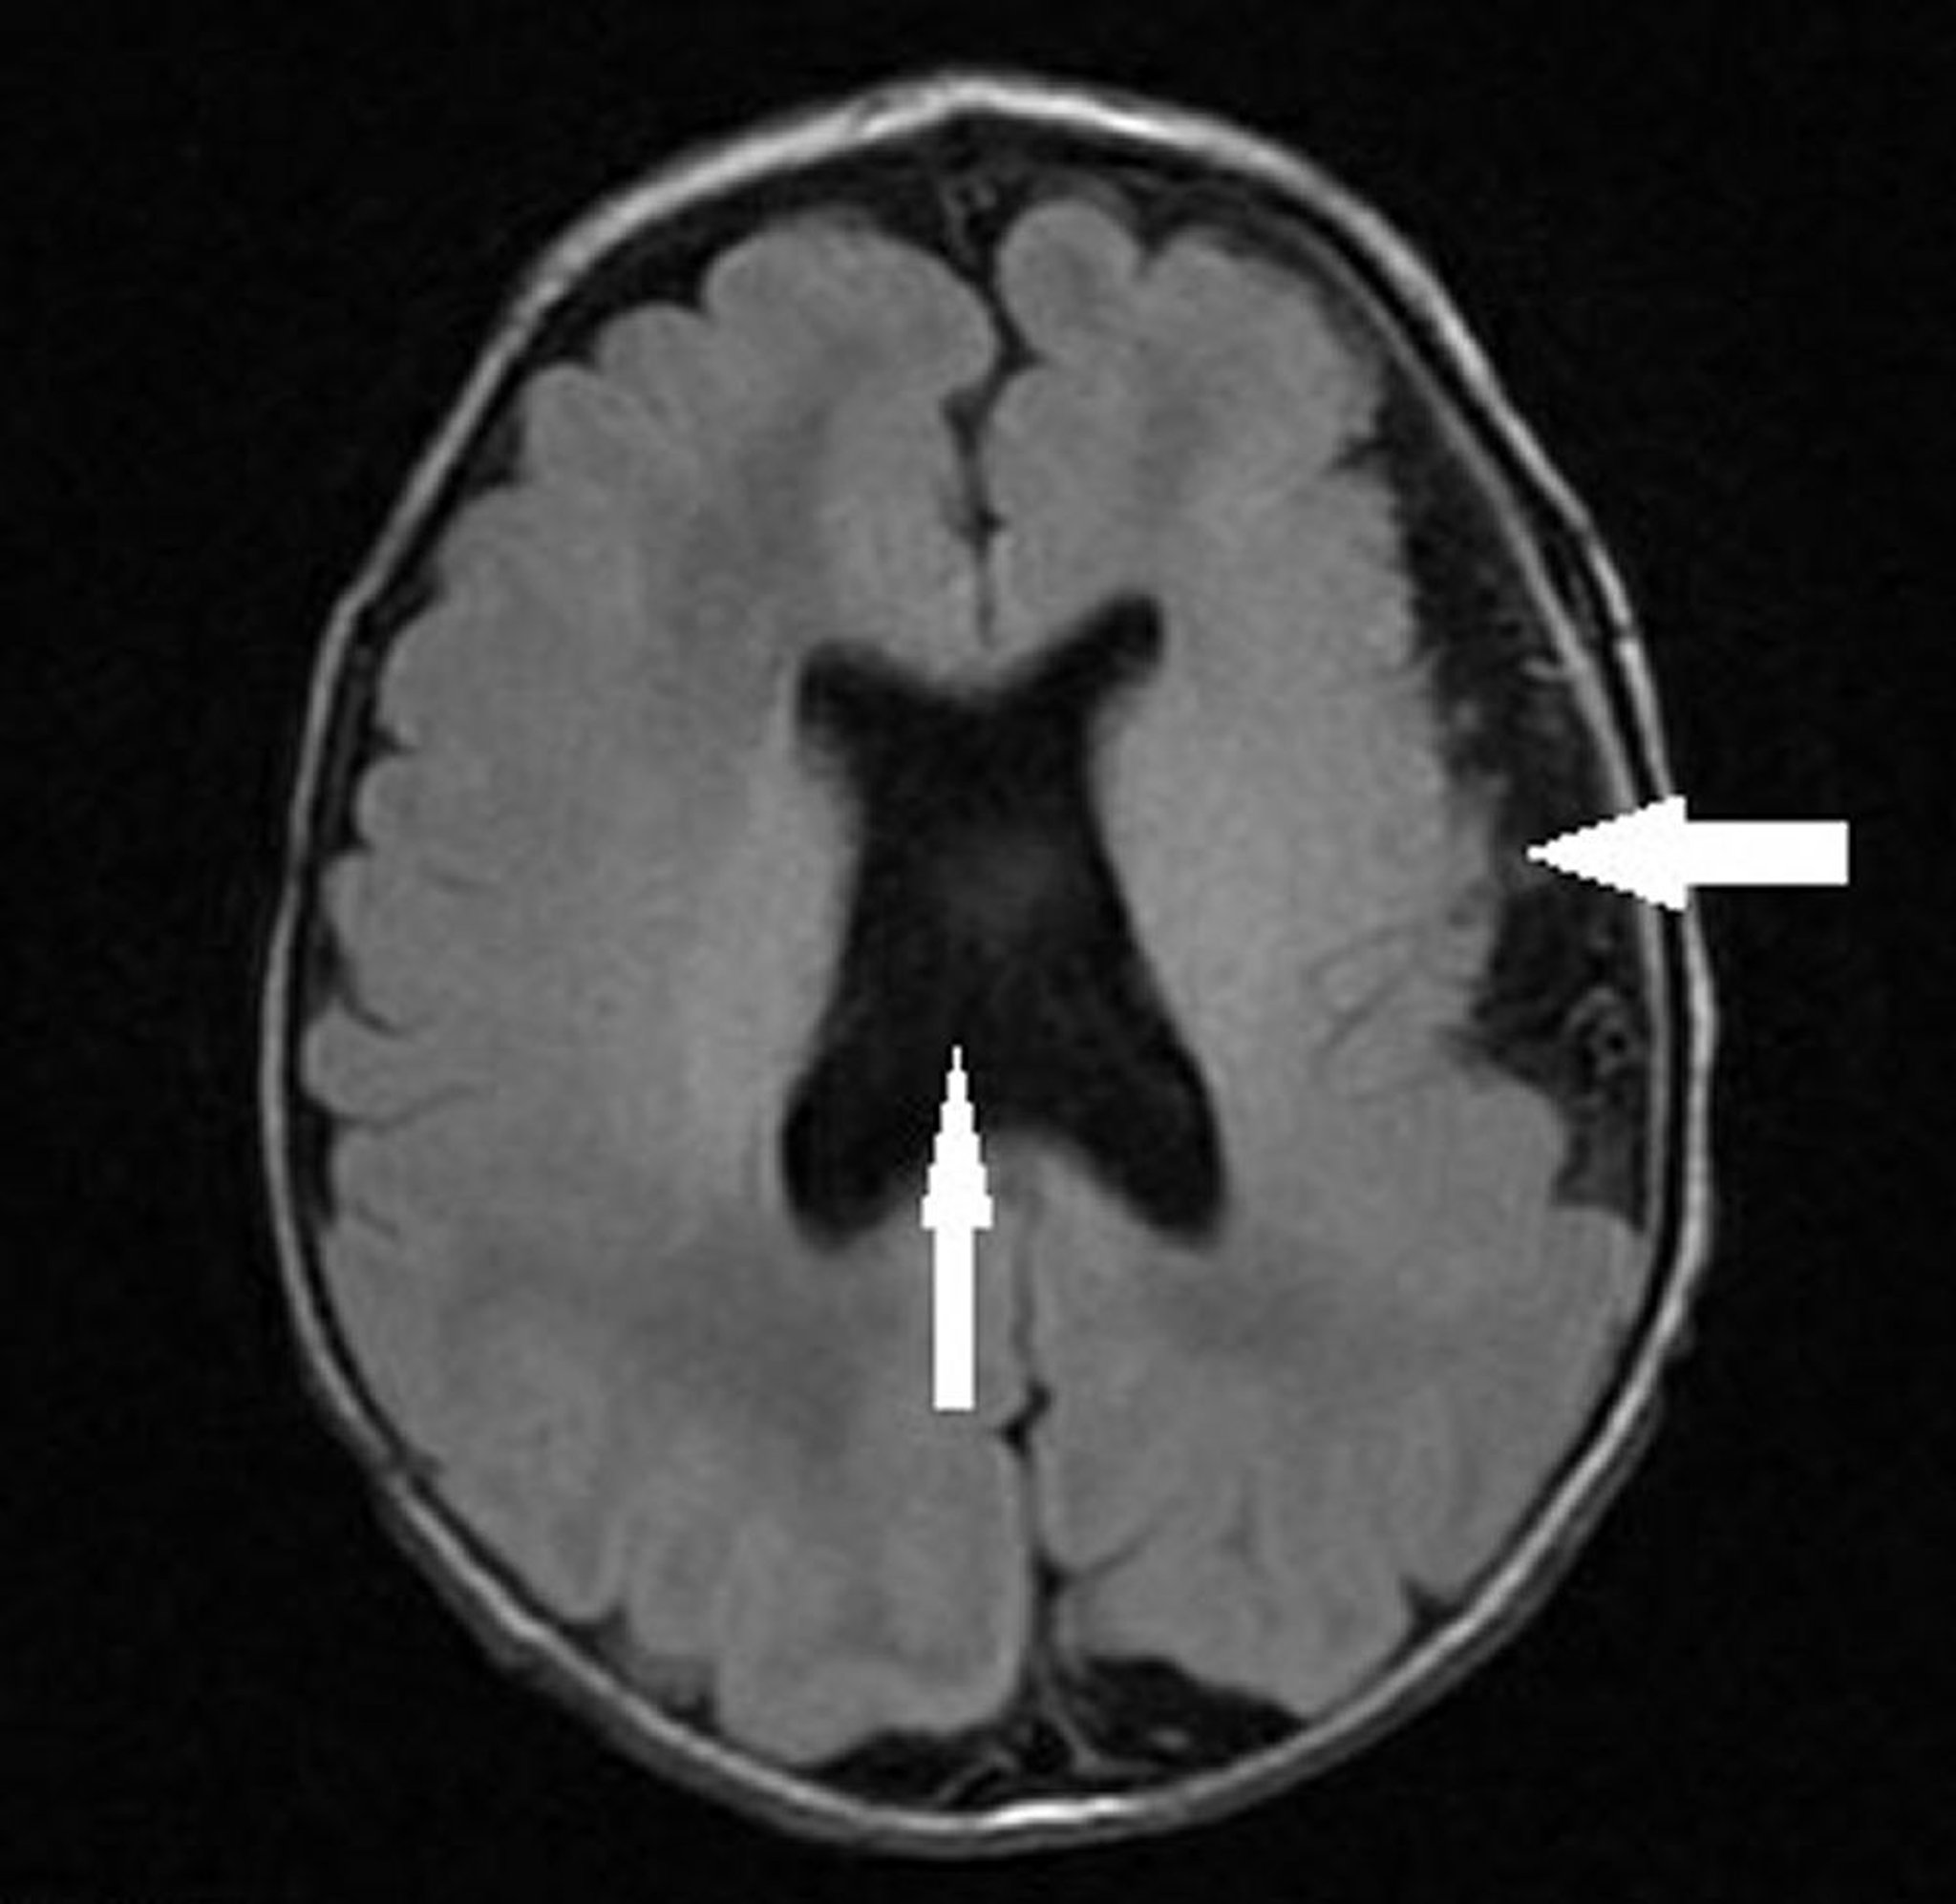

This image shows an infant with left hemispheric polymicrogyria (leftward arrow) and absent septum pellucidum with abnormal ventricular configuration (vertical arrow) consistent with septo-optic dysplasia (optic nerve hypoplasia, absent or abnormal septum pellucidum, and pituitary hypoplasia).

Image courtesy of Stephen J. Falchek, MD.